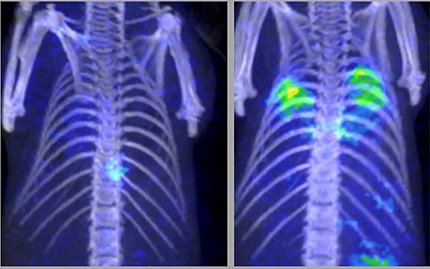

Scans of human lungs: one shows healthy lungs; the other shows bright green spots signaling fungal pneumonia

At r, lungs infected with fungal pneumonia

The radiolabeled cellobiose was eventually proven in animal models to be a specific imaging ligand for certain invasive fungi like Aspergillus.

After so many failed attempts with other sugars, when Hammoud and her lab finally saw high radioactive signal localizing to the fungal infection on PET after injecting the tagged cellobiose, they thought it must be a fluke. But it was the breakthrough they were hoping for. She and Swenson published their work in August 2024.